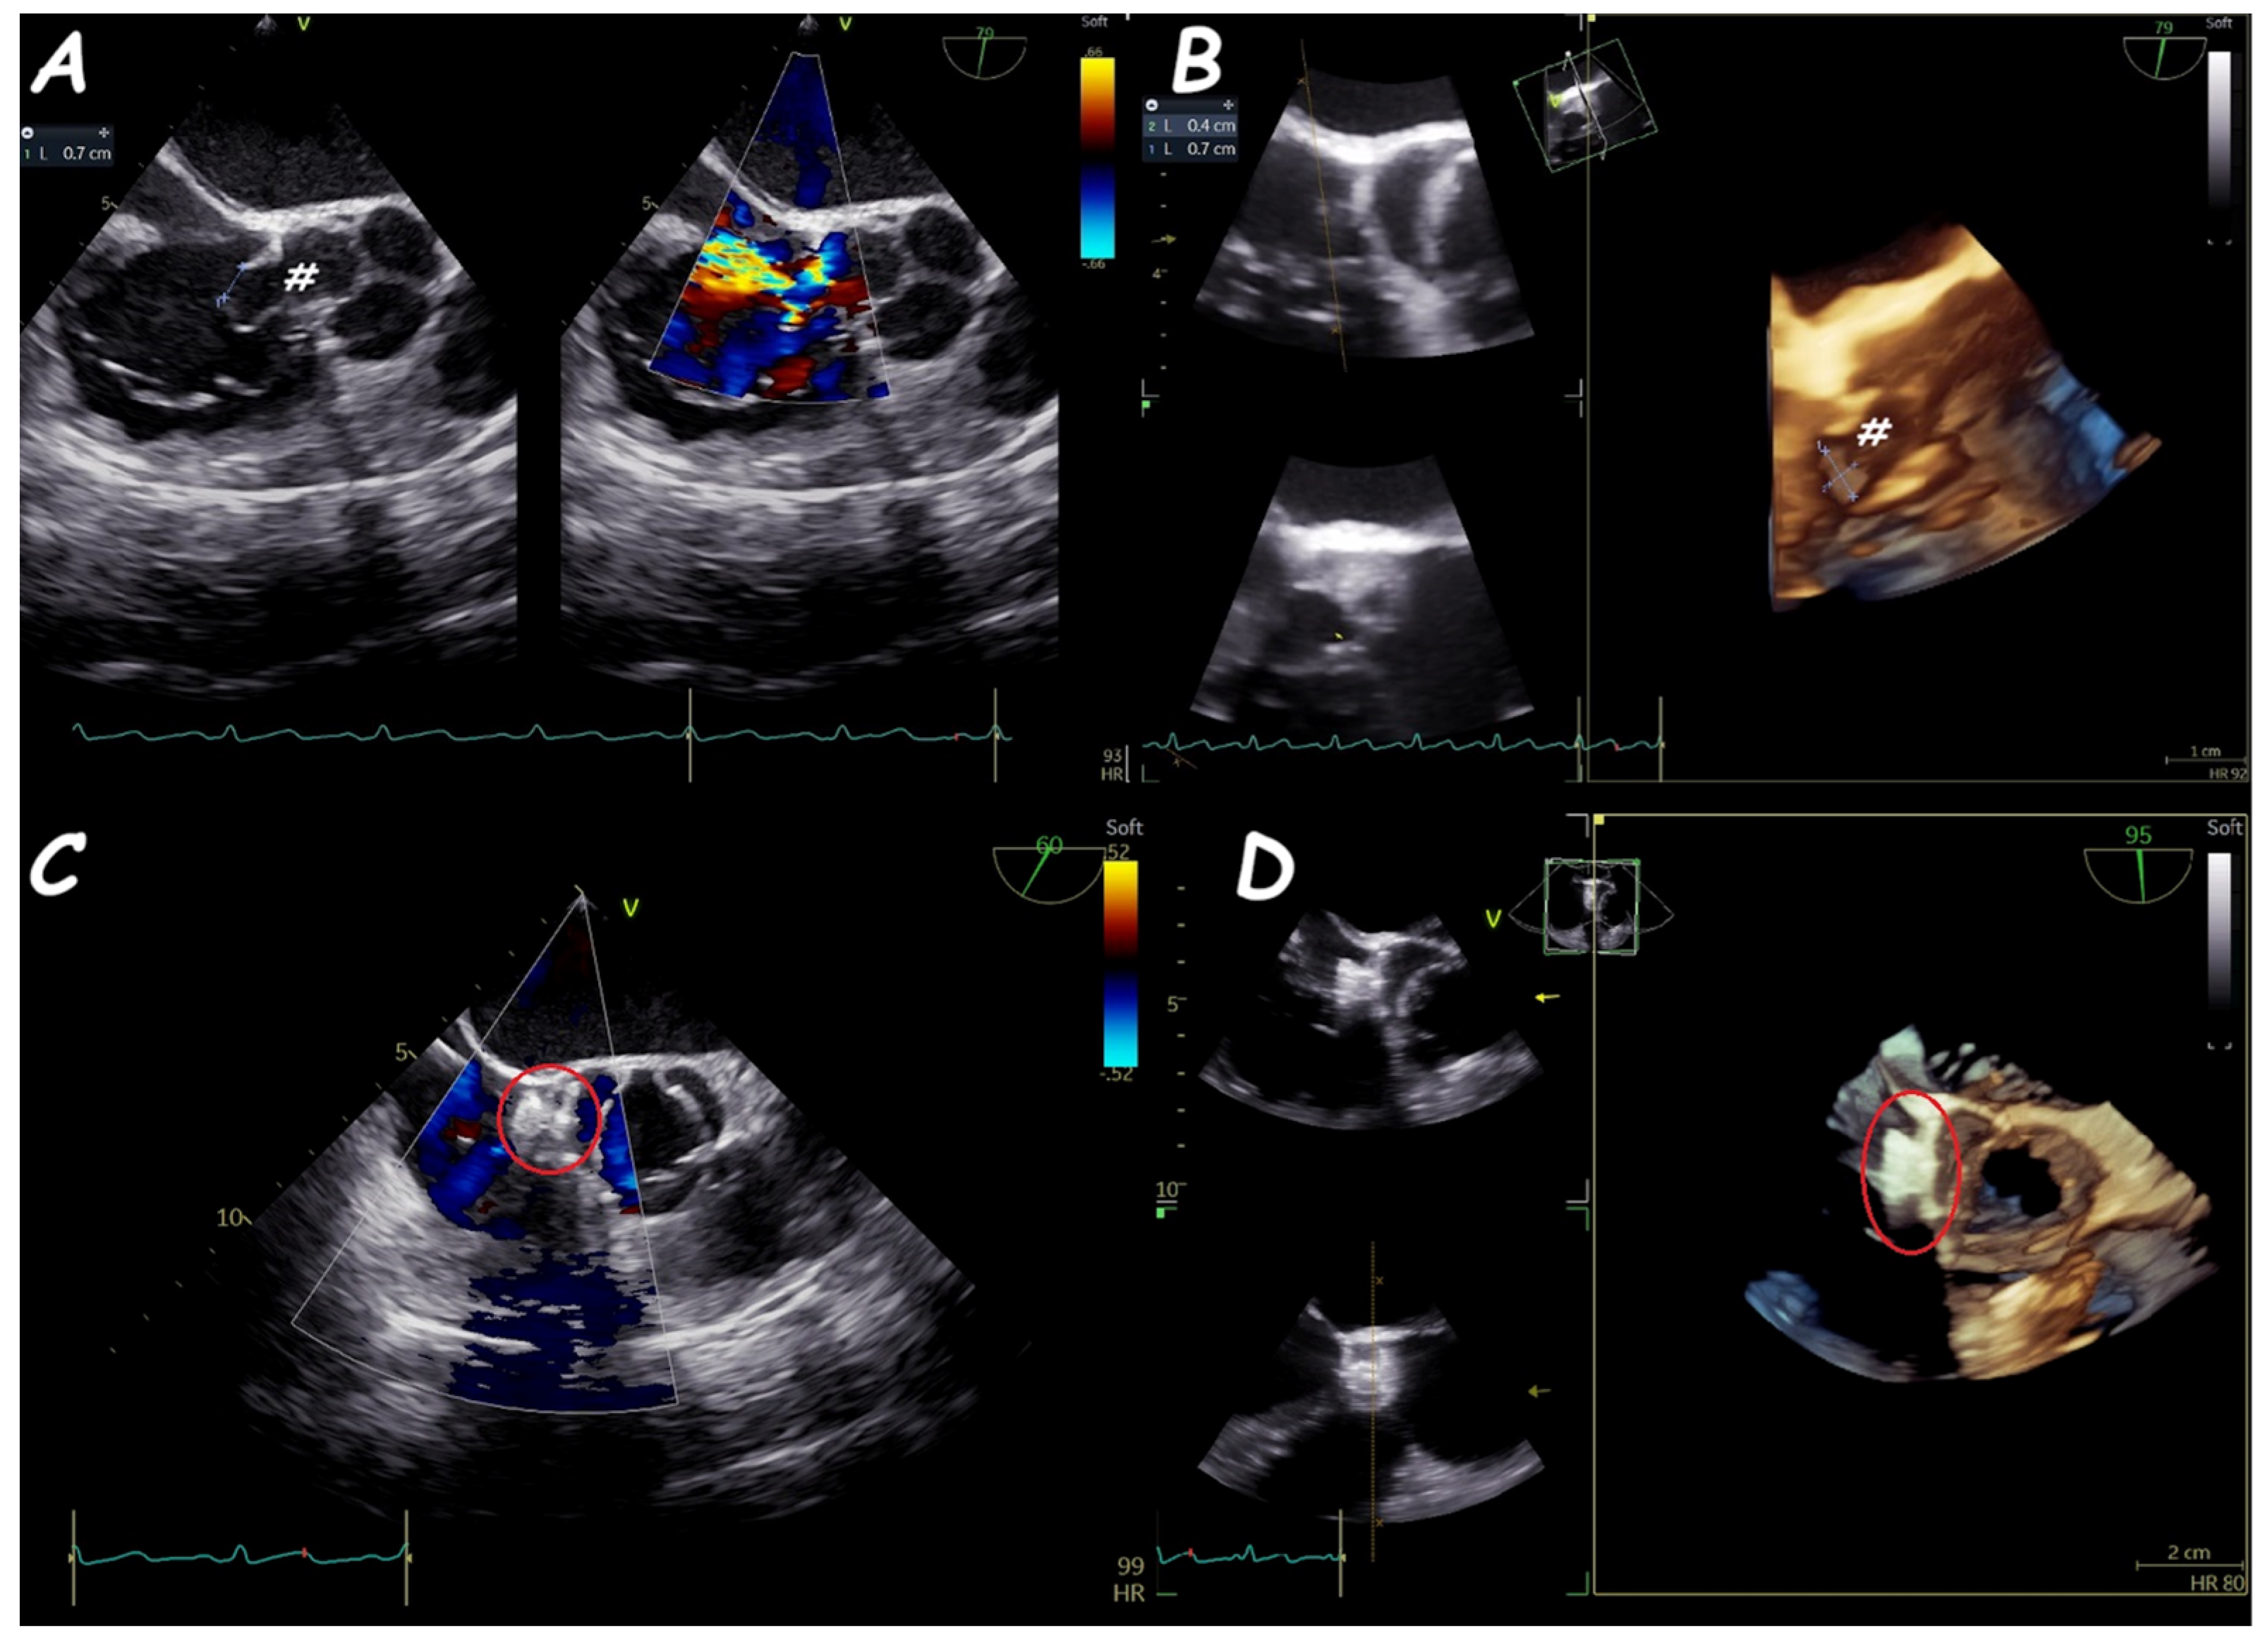

6. Ruptured Sinus of Valsalva Closure